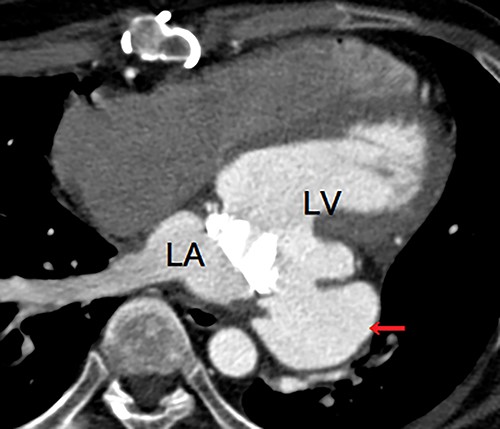

A 40-year-old man was referred to our hospital with suspected LVPA without any symptoms. He had a three-time history of mitral valve surgery, all of which due to infectious endocarditis (IE). Initial mitral valve repair was performed 8 years ago, and MVR were performed 7 years and 4 years ago. In addition, he had a history of severe atopic dermatitis. He had experienced another episode of IE 1 year ago, which was treated with antibiotic therapy. Enhanced computed tomography (eCT) at that time revealed a small nodular contrast region immediately below the mitral valve annulus in the left ventricular muscle. However, the evaluation could not clearly indicate an aneurysm at that point. Transthoracic echography (TTE) at our hospital revealed an LVPA that gradually expanded at the posterior wall immediately below the mitral valve annulus, and the mechanical prosthetic valve had normal function. eCT revealed a massive LVPA that was >50 mm in size (Fig. 1). We decided to close the LVPA due to a risk of future rupture. Thus, the patient underwent his fourth median sternotomy, through which a cardiopulmonary bypass was established with ascending aortic cannulation and bicaval drainage, and the heart was arrested with antegrade cardioplegia. The mitral prosthetic valve was visualized through a right-sided left atriotomy. After removing the valve, the orifice of the aneurysm was confirmed (Fig. 2). Unlike that in the case of active IE, the tissue around the aneurysm was not vulnerable; thus, the orifice was closed using a bovine pericardial patch (Fig. 3A). In addition, BioGlue (CryoLife Inc., Kennesaw, GA, USA) was injected into the aneurysm (Fig. 3B). The aneurysm was filled with BioGlue to prevent blood flowing into it. Thereafter, MVR was performed using a 25-mm On-X heart valve (CryoLife Inc., Kennesaw, GA, USA). Postoperative eCT revealed complete closure of the aneurysm (Fig. 4). The patient’s cardiac function was good, and no paravalvular leakage was observed on TTE. He was discharged home without complications. At the 10-month follow-up, the size of the aneurysm found to be reduced, as revealed using TTE.

Enhanced computed tomography showing a left ventricular pseudoaneurysm (arrow) just below the mitral valve annulus. LA, left atrium; LV, left ventricle.